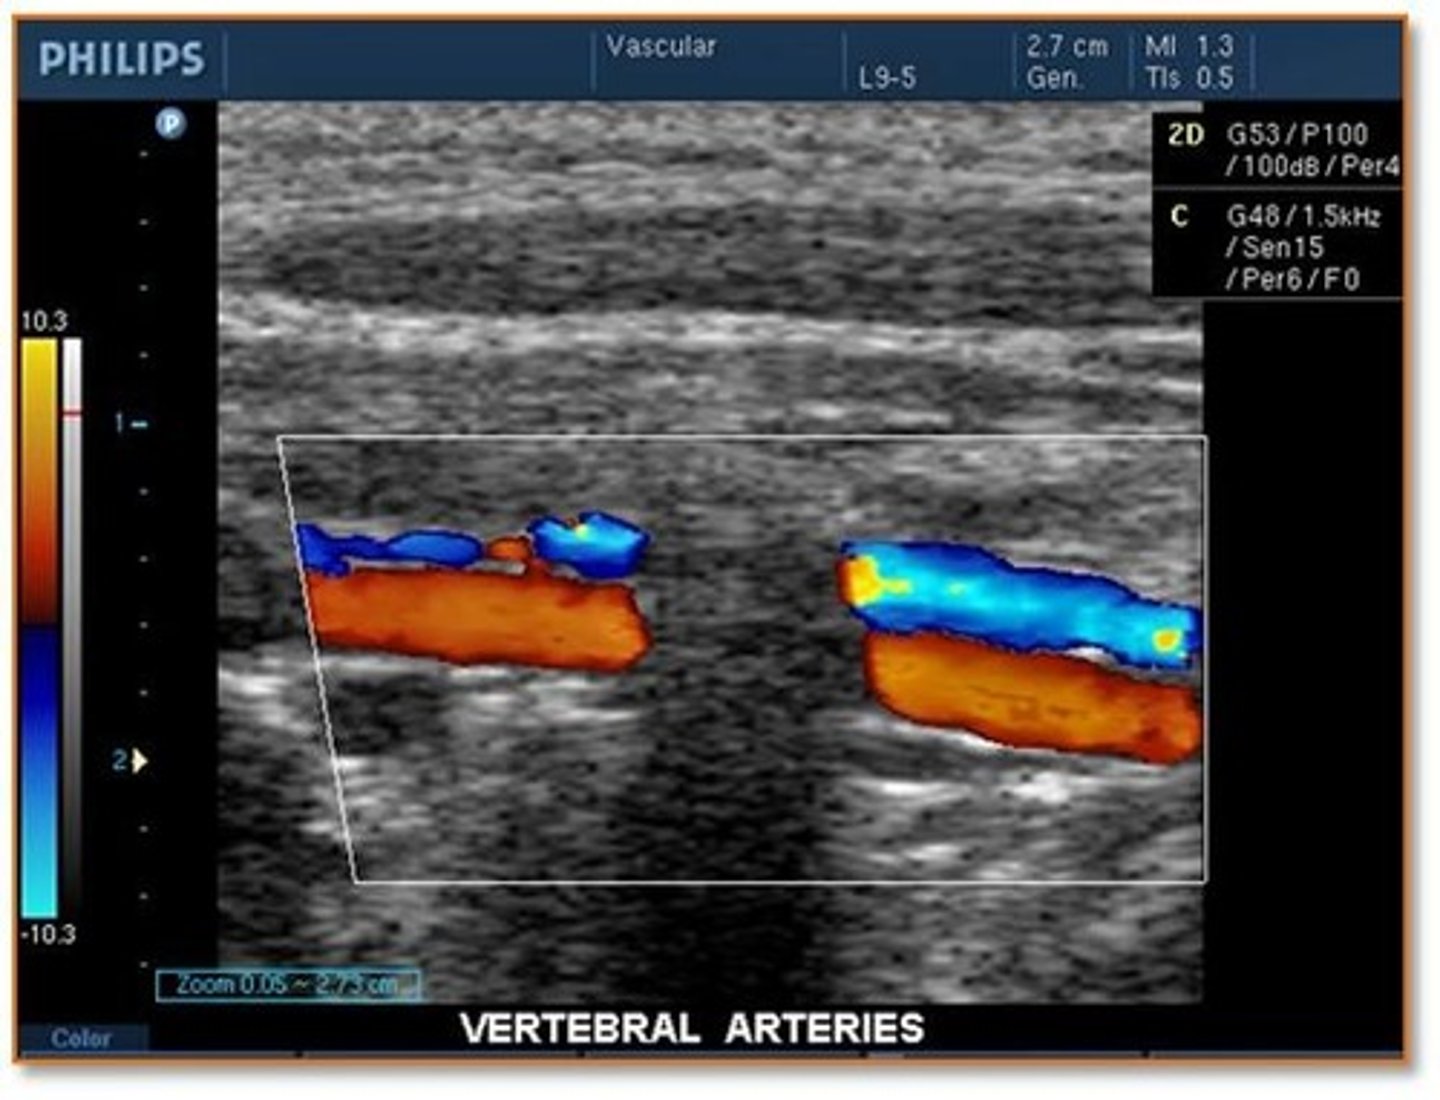

When scanning the cerebrovascular system (carotid arteries and vertebral arteries), the sonographer is ready to demonstrate flow in the vertebral arteries. What combination of ultrasound system adjustments should he/she make to properly visualize the vertebral arteries?

increase velocity scale and increase depth

decrease velocity scale and increase depth

decrease velocity scale and decrease depth

increase velocity scale and decrease depth

While scanning the vertebral arteries, the sonographer notes a significant shadowing effect through the vessel that interrupts the color Doppler information. How should the sonographer report this finding to the physician?

normal shadowing from the spinal processes

abnormal shadowing from plaque on the anterior wall of the vertebral artery